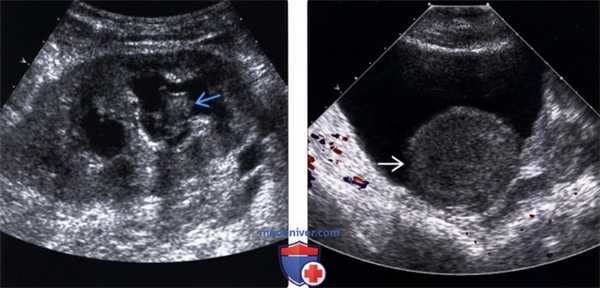

2. УЗИ при гидронефрозе трансплантата почки:

• Серошкальное ультразвуковое исследование:

о Расширенная, заполненная жидкостью почечная лоханка, переходящая в расширенные чашечки

о Может сочетаться с гидроуретером и приводить к образованию бессосудистой цилиндрической структуры, проходящей от ворот почки до мочевого пузыря

о Помните, что растянутый мочевой пузырь может вызывать функциональную обструкцию или рефлюкс, приводящие к гидронефрозу:

- Повторное исследование после опорожнения пузыря

о Гипоэхогенные сигналы в просвете позволяют предположить гной (пионефроз) или кровь (гемонефроз):

- Также в мочеточнике и мочевом пузыре может локализоваться тромб

- Взвесь при инфекции может быть многослойной

о Гиперэхогенные очаги в просвете с акустическим затенением представляют собой конкременты:

- Тем не менее, мелкие конкременты иногда сложно визуализировать

о Гиперэхогенные образования со слабым затенением представляют собой мицетому

о УЗИ-чувствительный и специфичный метод выявления гидронефроза

о УЗИ ограничен определением только места обструкции без предоставления функциональной информации

• Цветовая допплерография:

о Используется для дифференцирования сосудов ворот почки от расширенной почечной лоханки

о Цветовая допплерография позволяет дифференцировать тромб или взвесь от солидной опухоли:

- Применяется для визуализации мелких сосудов в уротелиальных опухолях

о Повышенный индекс резистентности (ИР) > 0,7 может возникать при обструктивной уропатии, однако ИР-неспецифичен и редко имеет диагностическое значение

о Артефакт мерцания позволяет точно диагностировать конкремент